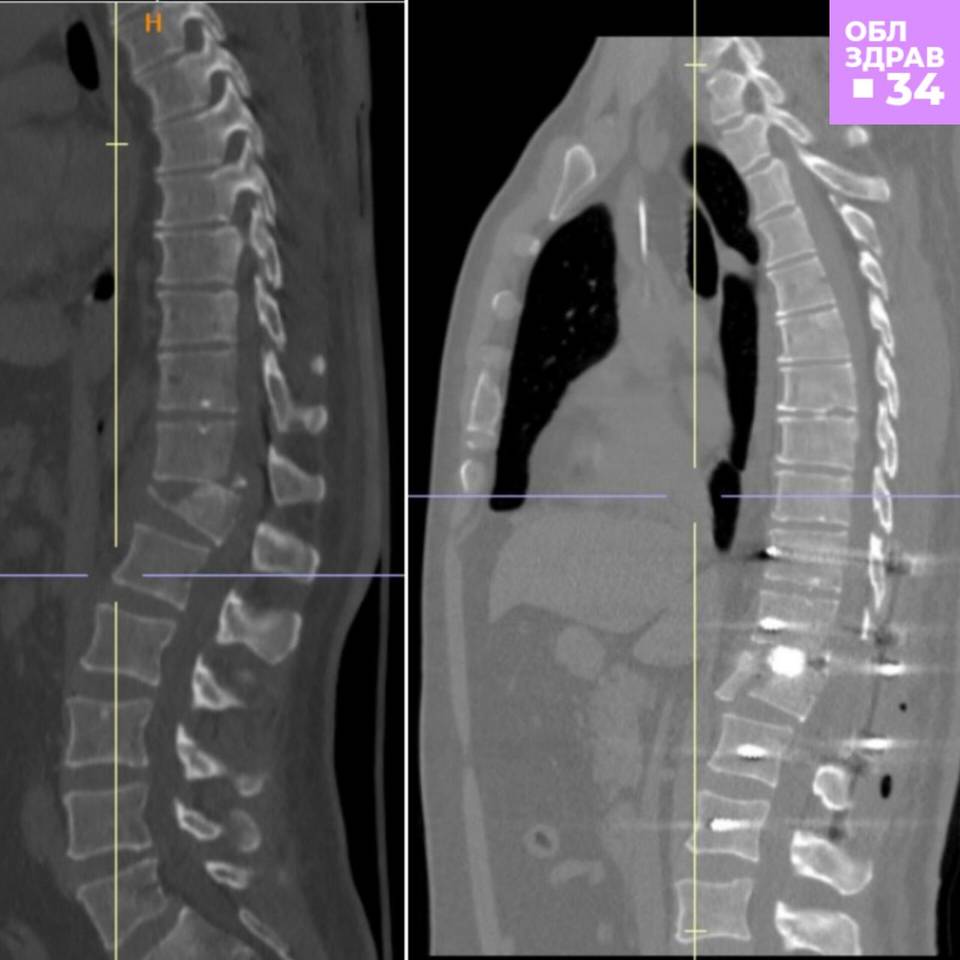

В облздраве "Городским вестям" уточнили: травма была производственная. У мужчины, который поступил на скорой в Волгоградскую областную клиническую больницу №1, специалисты диагностировали компрессионно-оскольчатый перелом позвонка, а также открытый перелом нижней трети костей левой голени со смещением. закрытый перелом ребер и тупую травму грудной клетки. Как говорится, полный набор.

Нейрохирурги без промедления провели операцию, выполнив целый ряд сложных медицинских манипуляций. В том числе был установлен специальный имплант, взявший на себя опорную функцию позвоночника до полного срастания позвонков. Установили специалисты и титановые винты для того, чтобы на период консолидации переломов создать дополнительную опору.